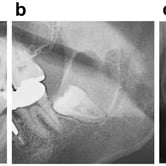

Dientes impactados

Los dientes impactados son dientes que no pueden erupcionar correctamente debido a la falta de espacio o a una obstrucción.

Los pacientes pueden notar que un diente no ha salido, aunque debería haberlo hecho. Esta condición es común con las muelas del juicio y los caninos superiores.

El tratamiento puede incluir la extracción del diente impactado o la creación de espacio para permitir su erupción.